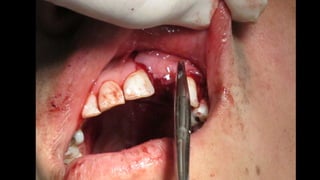

El documento trata sobre la cirugía bucal para plastía del proceso alveolar utilizando hueso humano y factores de crecimiento. También menciona los cuidados postoperatorios, que incluyen el uso de hielo, reposo, dieta líquida y antibióticos, evitando antiinflamatorios no esteroides. Se proporciona información adicional sobre las páginas web relacionadas con cirugía maxilofacial.